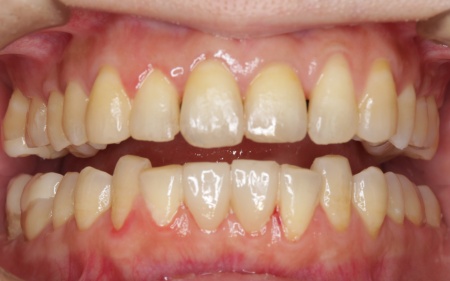

矯正治療が終了したあと、セラミックによる修復治療へと移行しました。 さらにすり減って形が不揃いになっていた下中央の前歯2本には、ラミネートベニアと呼ばれる歯の表面に薄いセラミックの板を貼り付ける方法を用いて形を調整しました。 以上の工程を順に進め、すべての治療を終了しました。 |

治療後